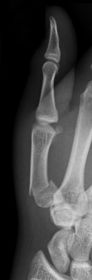

| Lateral Digit | finger bent back - not truly lateral |

| What's the evaluation criteria for the Lateral finger x-ray? | ANATOMY: entire digit demonstrated CRITERIA: open joint spaces concave to one side, while the dorsal side is straight no overlapping of adjacent fingers/soft tissues POSITIONING: CR perpendicular @ PIP joint |